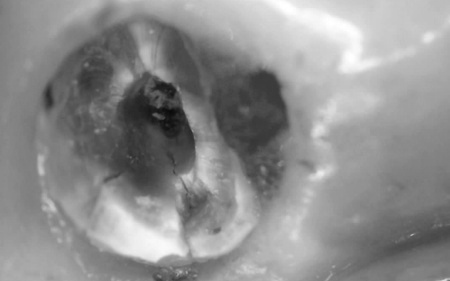

もともと入っていた古い被せ物を除去すると、歯根に亀裂が入っていました。こちらも歯の温存が難しいと判断し、抜歯処置を行いました。